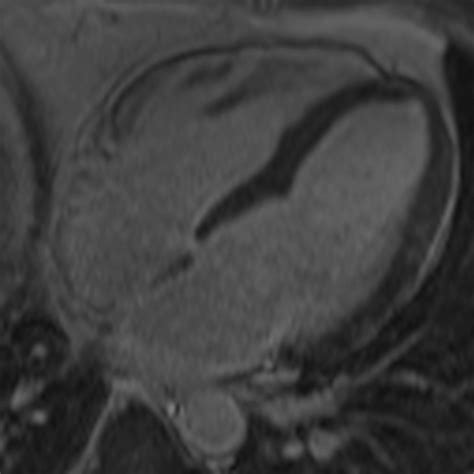

• Cardiac magnetic resonance imaging (MRI) to detect inflammation and damage

• Advanced imaging techniques, such as cardiac MRI and PET scans